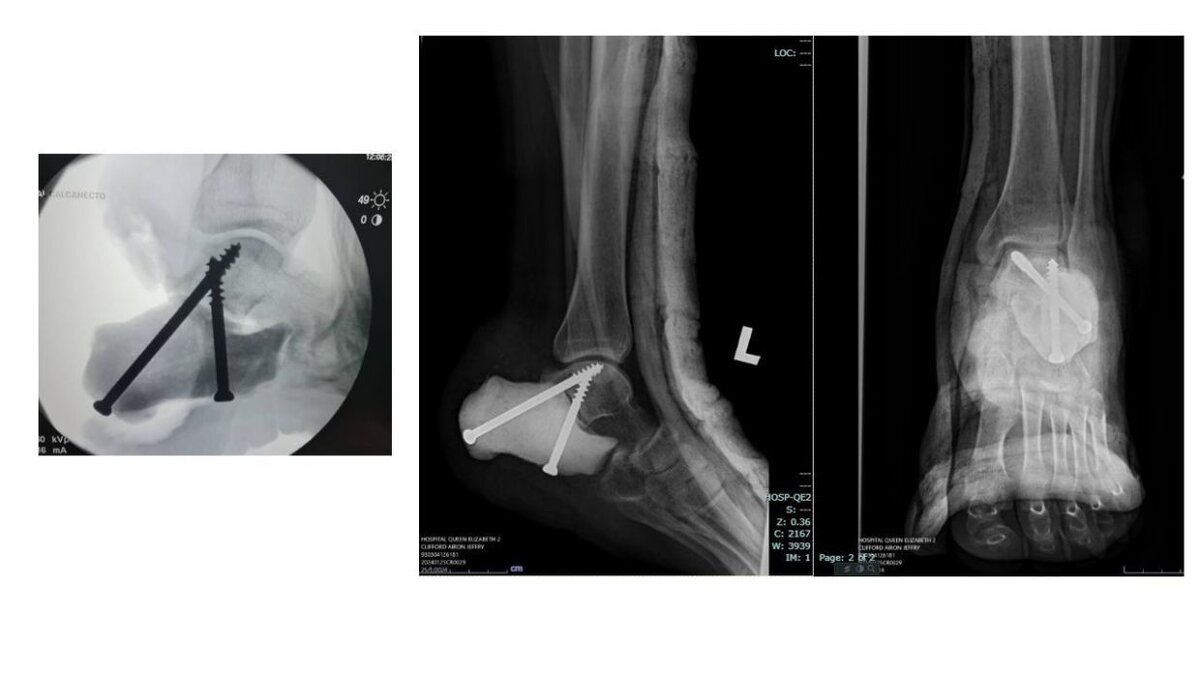

Малазийские онкологи недавно достигли важной вехи, успешно проведя первую в стране замену пяточной кости с использованием 3D-печатной формы. Процедура была направлена ​​на устранение рецидива леченной гигантоклеточной опухоли, что требовало полной резекции пяточной кости. Выздоровление пациента без осложнений подчеркивает эффективность этого метода. Благодаря своей экономической эффективности подход 3D-печати становится многообещающим решением для реконструкции костей в условиях финансовых ограничений в государственных медицинских учреждениях. Медицинская команда подчеркивает универсальность метода, подчеркивая его потенциал принести пользу многочисленным пациентам, нуждающимся в реконструкции костей. Операция, возглавляемая врачами отделения ортопедической онкологии, под руководством доктора Аарона Жерарда Пола, доктора Эйрика Го Боай Хонга и доктора Ти Кок Кита, ознаменовала значительный скачок в медицинских инновациях. Подготовка включала тщательное планирование и использование пер

Операция, возглавляемая врачами отделения ортопедической онкологии, под руководством доктора Аарона Жерарда Пола, доктора Эйрика Го Боай Хонга и доктора Ти Кок Кита, ознаменовала значительный скачок в медицинских инновациях. Подготовка включала тщательное планирование и использование передовых технологий для преобразования изображений КТ в точные 3D-модели.

Для печати в формах использовалась полимолочная кислота (PLA), чтобы обеспечить биосовместимость и простоту стерилизации. В форму заливали костный цемент из полиметилметакрилата (ПММА), который обеспечивал бесшовное крепление, позволяя выдерживать послеоперационную нагрузку.